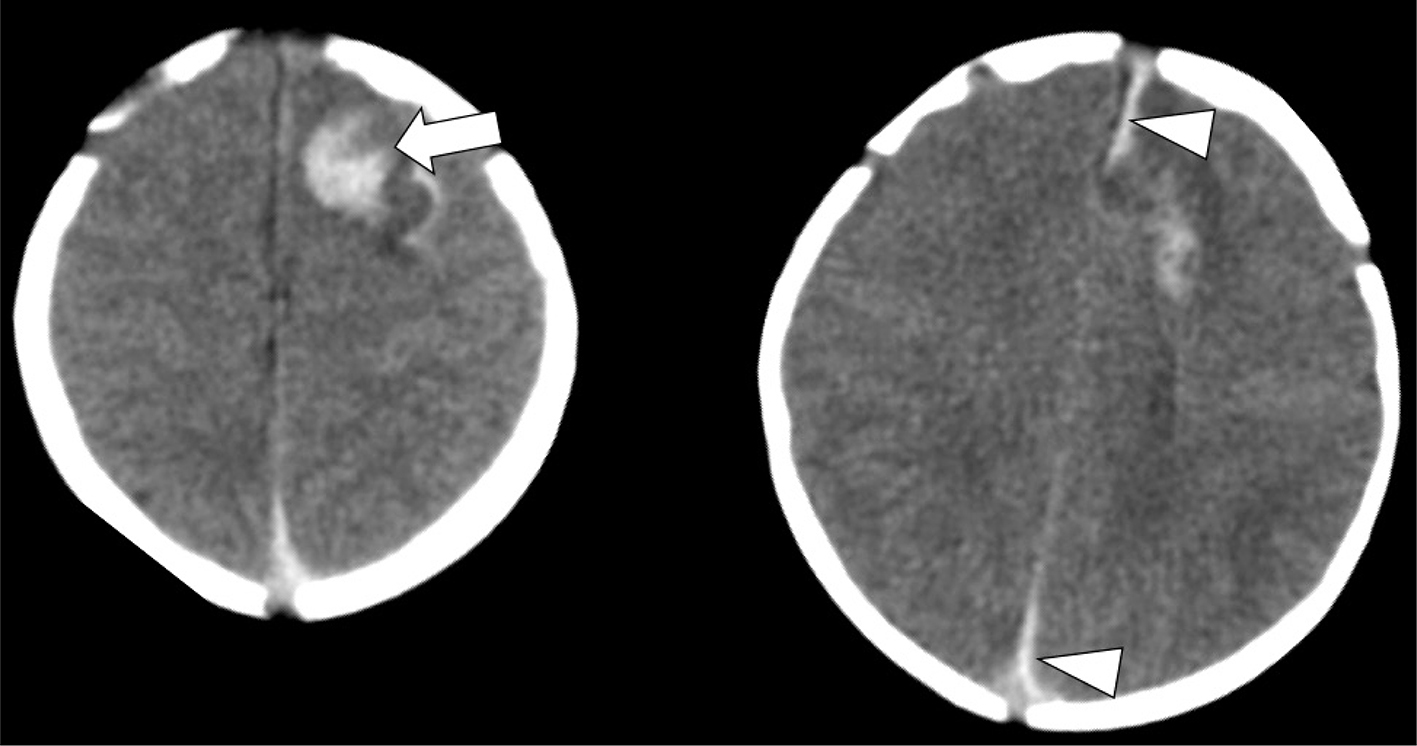

On MRI, acute infarcts demonstrate reduced diffusivity within minutes, exhibiting high signal on DWI and low computed diffusivity on ADC maps (Figure 5) (46). Diffusivity remains reduced for about 6 days, peaking at about 3 days, before pseudonormalization occurs, with diffusivity then increasing to above normal by the second week (4750). Timing of DWI changes can be affected by the age of the patient, size of the stroke, and how quickly collateral blood flow is recruited. DWI also detects early or pre-wallerian degeneration in infants (also referred to as “acute network injury”), characterized by injury to the antegrade white matter tracts following acute infarct and manifests as reduced diffusivity in white matter pathways affected by the infarction within a few days of the injury (Figure 5) (51). Common pathways affected by acute network injury include the corpus callosum, thalamus, and descending corticospinal tract. When seen along the corticospinal tracts, acute network injury is highly predictive of poor motor outcomes (52, 53).

Figure 5. Acute neonatal arterial ischemic infarction in a three-day-old girl with seizures. Axial DWI (A) and (B), and axial ADC (C) images show extensive area of reduced diffusion in the left MCA territory (arrows). Arrowheads (A, B, C) indicate pre-Wallerian degeneration in the posterior limb of the internal capsule and left cerebral peduncle along the corticospinal tract. D. 3D time-of-flight MRA shows abrupt absence of flow in the left MCA (arrow). Axial T2-weighted image (E) at 5-month follow-up shows extensive encephalomalacia and volume loss in the left MCA territory. Case courtesy of Dr. Tamara Feygin, Department of Radiology, Children’s Hospital of Philadelphia.